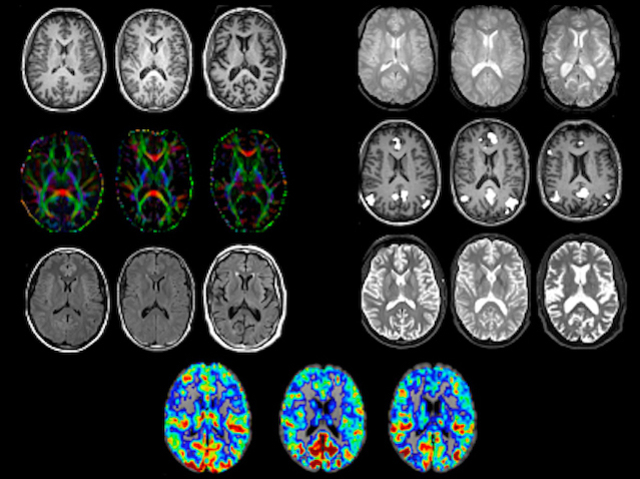

Sharing Brains

Brain imaging resource of data collected from individuals genetically inheriting predisposition to Alzheimer's disease provides insight into the onset in the much larger population who develop the disease sporadically and into brain ageing generally